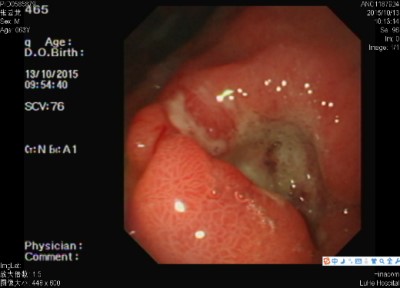

二、胃癌

胃癌病因目前尚不十分清楚。就目前研究资料得知,胃癌的发生与下列因素有关:(1)饮食与生活习惯:咸菜、腌肉、熏制食物为主要副食者,胃癌发病率显著增高。副食品中以蛋白质、新鲜蔬菜、水果摄入量多,则胃癌发生率就明显降低。(2)环境因素:流行病学调查发现,土壤及饮水中缺乏微量元素(如铜、锰、锌、硒、镁)的地区,胃癌发病率就增高。(3)免疫因素:凡免疫功能低下者,胃癌发病相对增高,(4)遗传因素:多数回顾性调查资料认为,胃癌有明显的家族聚集倾向。一般认为,胃癌病人亲属的胃癌发病率比对照组高4倍。(5)感染因素:幽门螺杆菌感染的高危人群患胃癌的危险性较低感染者高6倍。(6)其他因素:许多疾病被认为与胃癌的发生有关,如慢性萎缩性胃炎、慢性胃溃疡、胃息肉等。

胃癌的早期信号:(1)年龄40岁以上,以往无胃病史,突然食欲减退,饭后饱胀,上腹部隐痛或消瘦(2)以往胃病表现的规律疼痛突然改变,按胃溃疡治疗效果不佳。(3)平时胃酸少,爱吃酸性食物或经确诊为萎缩性胃炎或不典型增生,病史较久,又突然消瘦、贫血、怕吃油腻或消化不良症状加重。(4)年龄40岁以上,消化道出血(呕血或黑便),或连续化验大便隐血阳性持续两周以上。(5)胃溃疡经正规治疗两个月以上不愈者。(6)进行性消瘦及贫血者。